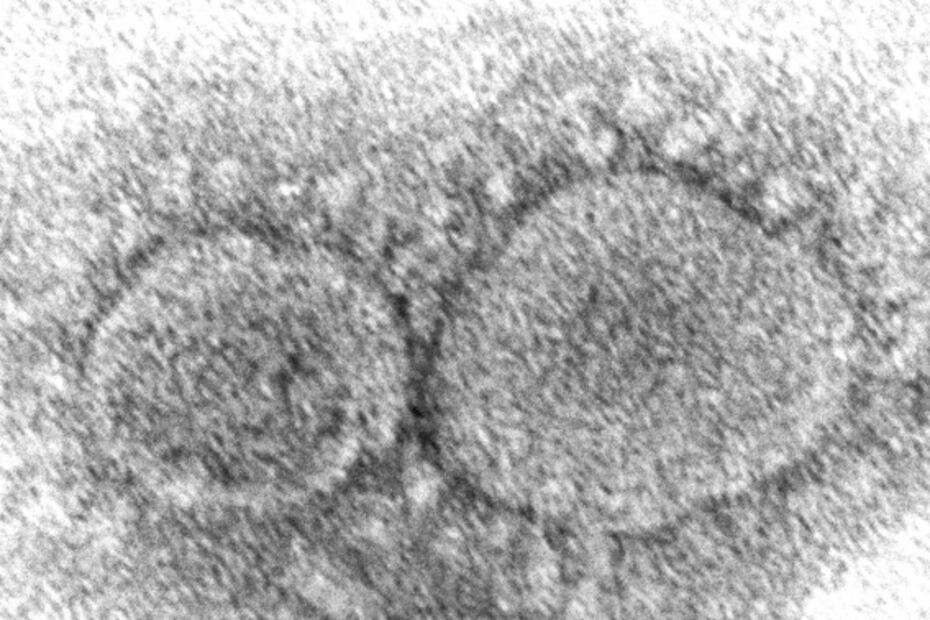

Foto: Hannah A. Bullock, Azaibi Tamin/CDC via AP